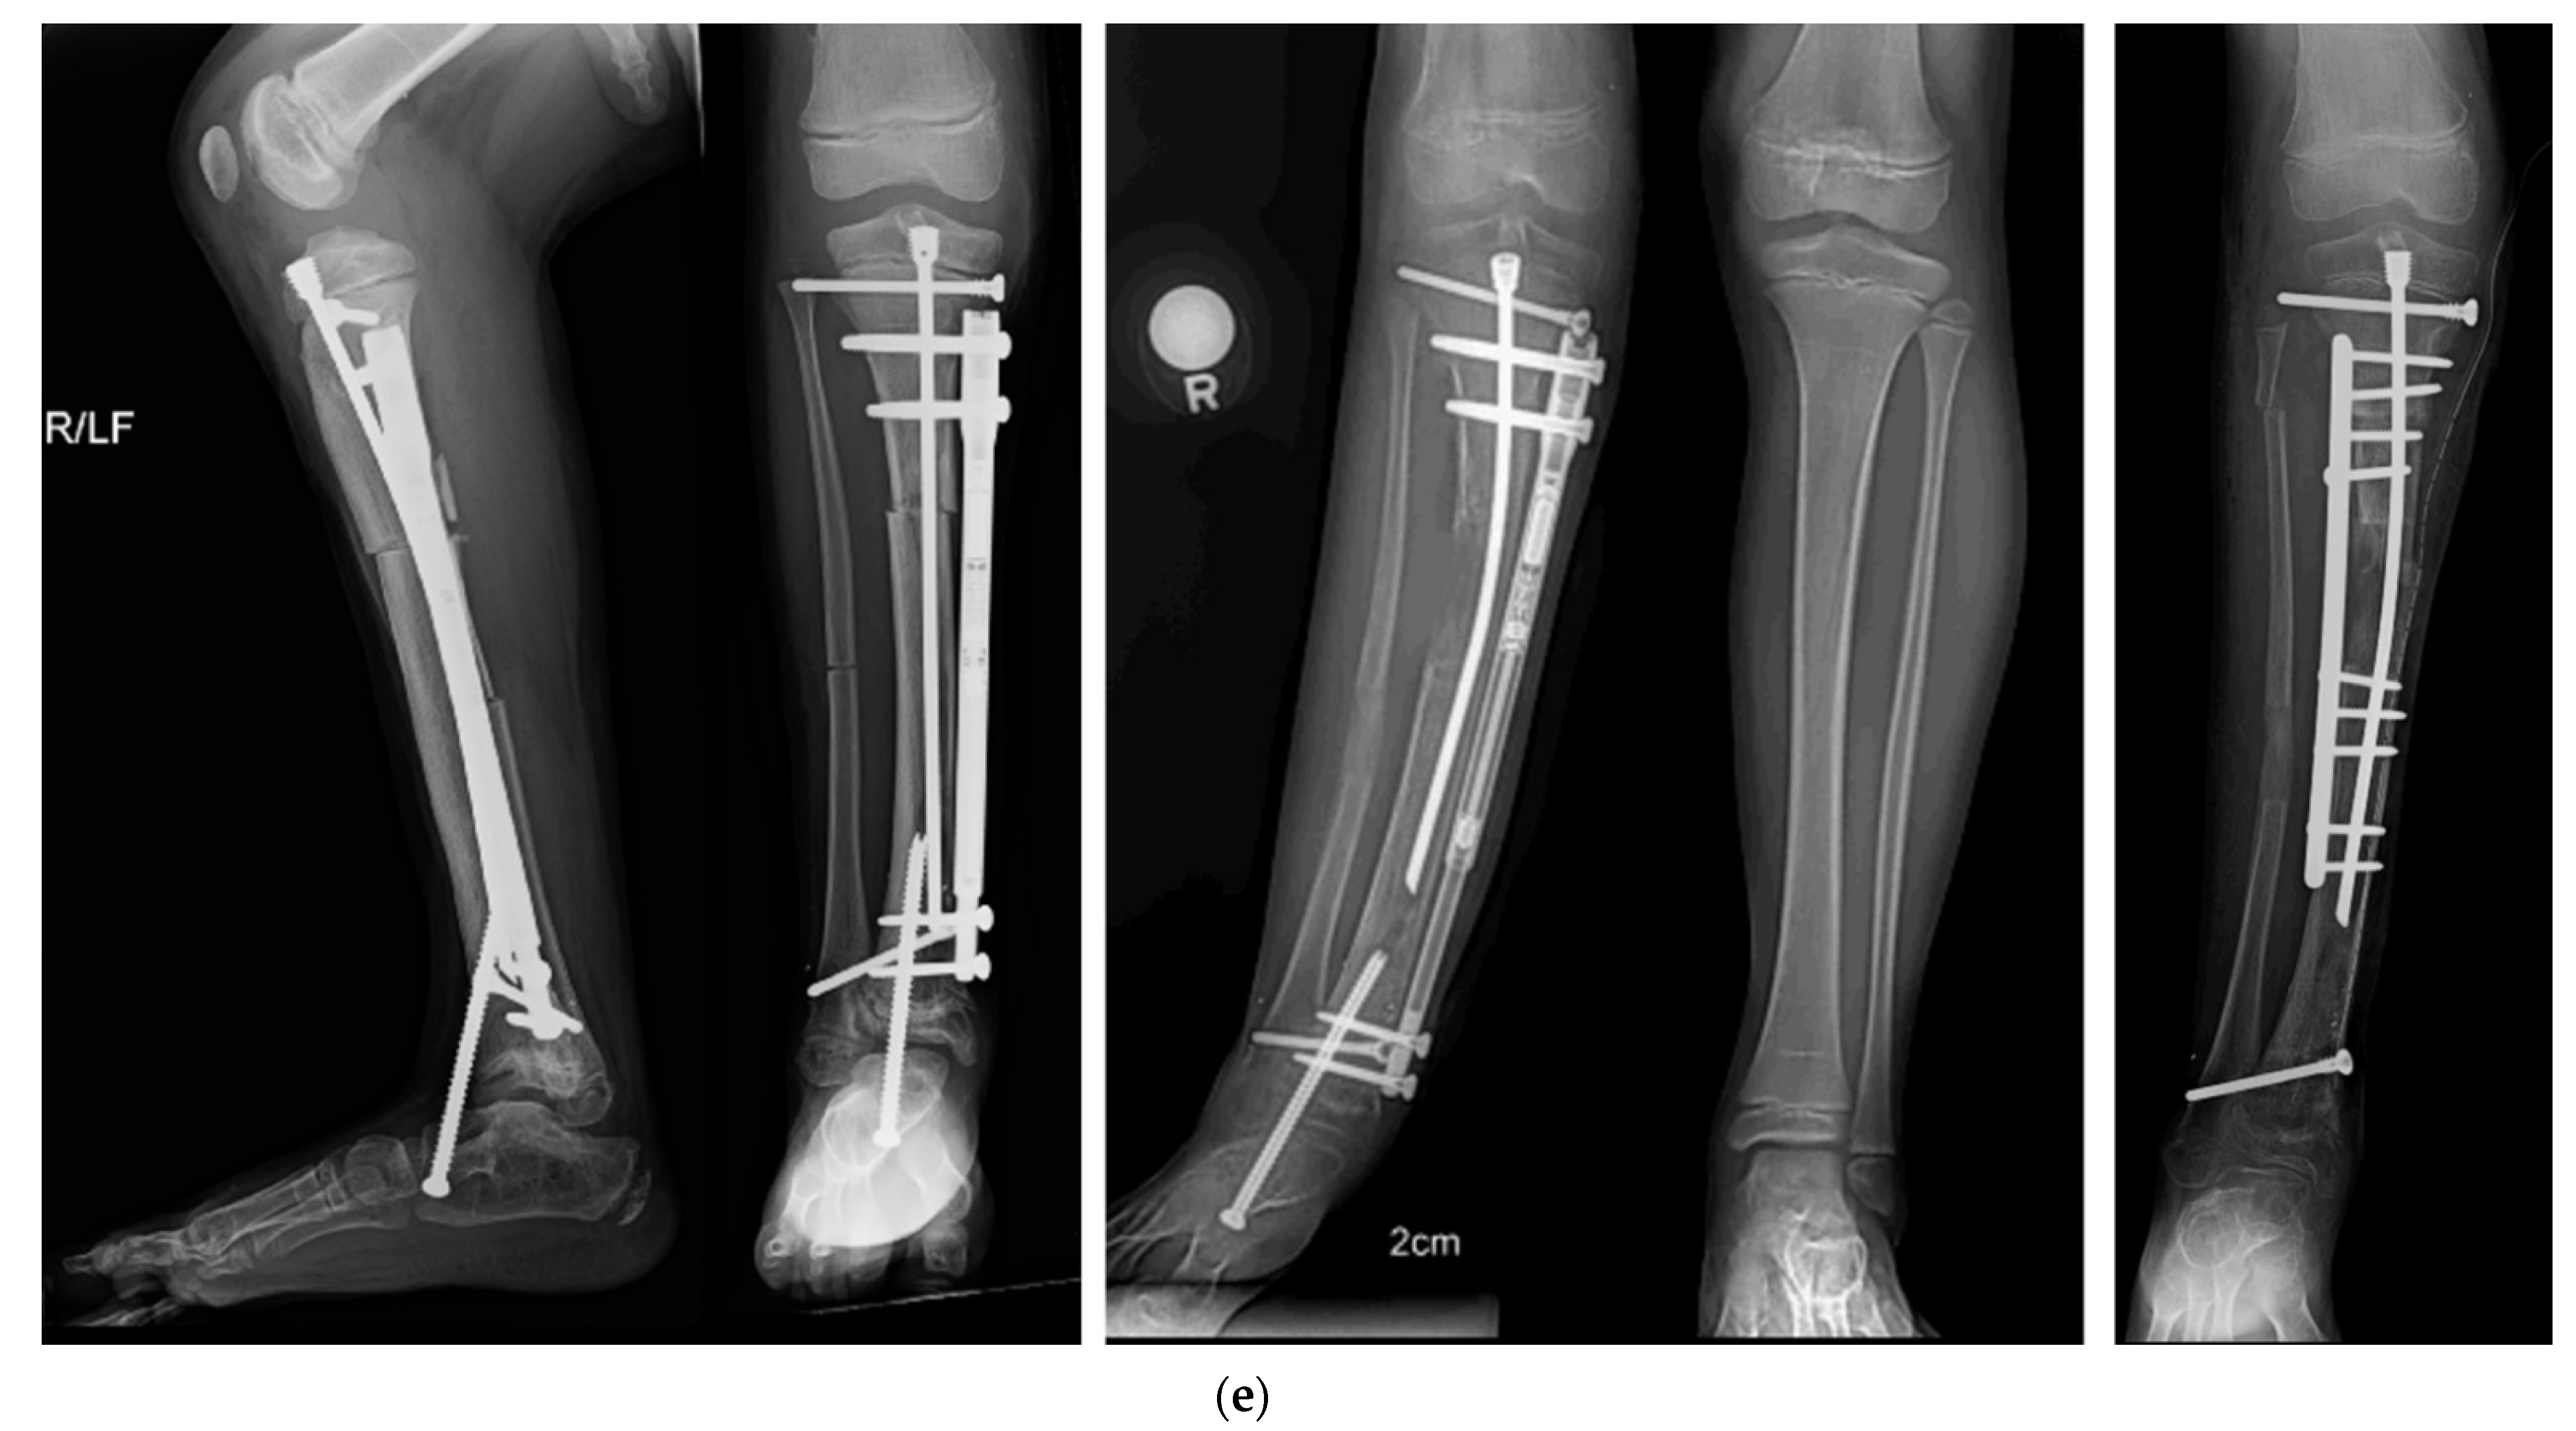

Figure 7.

(a) AP and lateral radiographs of 18-month-old girl with Paley type 3b1 FH. She has a rocker bottom foot and obvious subtalar coalition malunion. (b) Intraoperative fluoroscopic views showing splitting of subtalar coalition with an osteotome (left) and after shortening of tibia relative to fibula with plate fixation (SHORDT) combined with subtalar coalition malunion reduction and pinning. (c) Radiograph showing lengthening of tibia with computer dependent external fixator at the same surgery as the SUPERankle procedure. A hemiepiphysiodesis plate was also placed to treat the distal femoral valgus. (d) Final radiographs after removal of external fixator and after correction of proximal tibial valgus with a hemiepiphysiodesis plate. Note the stable appearance of the ankle joint and the plantigrade foot position. (e) Radiographic sequence of extramedullary lengthening with medially placed Precice nail (Nuvasive Specialized Orthopedics, California) (left). There is a Simple Locking IntraMedullary (SLIM) rod (Pega Medical, Montreal, Canada) and the fibula is fixed with tibio-fibular screws. The foot is fixed with a temporary extra-articular spanning screw from the foot to the tibia anterior to the ankle joint. A 5 cm lengthening was performed causing axial deviation into valgus bending the SLIM rod (middle). To correct the valgus, a plate was inserted laterally, and the extramedullary nail removed, after first decompressing the peroneal nerve, performing an anterior compartment fasciotomy and cutting the fibula proximally (right).